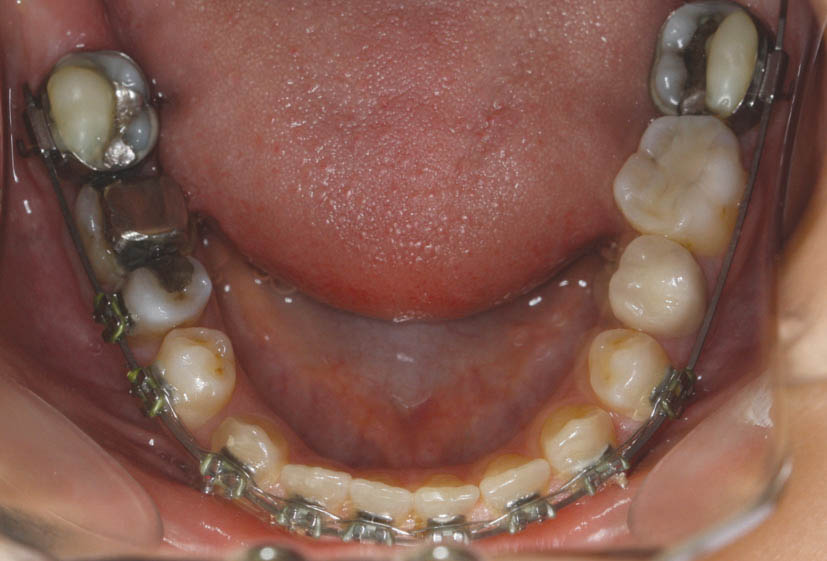

در زمان نزدیک شدن لترال به قوس فکی اگر به دندانهای پائین گیر کند باید از بایت پلیت خلفی (کامپوزیت روی کاسپهای باکال 7های پایین) استفاده کنید (شکل 161-1).

شکل 161-1: قراردادن کامپوزیت روی کاسپهای باکالی مولر دوم پایین برای ساختن بایت پلیت خلفی در هنگام حرکت دندانهای کراس به حالت نرمال